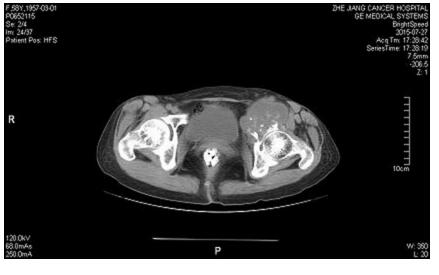

根据CT可见肿瘤累犯髋臼、耻骨下支、坐骨及部分髂骨,结合术前穿刺病理考虑软骨肉瘤,软骨肉瘤放化疗不敏感,手术为唯一根治性治疗手段,但耻骨上支后方闭孔动静脉与髂外或腹壁下动静脉会存在异常的吻合支,被称为“死亡之冠”,一旦不小心切断,很难实现止血,但是巨大的肿瘤往往遮挡手术的操作空间,很难有足够清晰的视野暴露血管,稍有不慎就将带来汹涌的出血并会危及生命。李涛主任带领整个团队经过术前反复讨论、缜密设计和充分准备,给病人实行了左骨盆肿瘤切除+全髋置换+髋臼修复+骨盆生物力学重建术,该术式利用自身骨质重建骨盆环,具有骨性愈合的特点,可以有效避免目前流行的单纯骨盆假体置换造成假体松动,脱位从而导致手术失败的缺点。